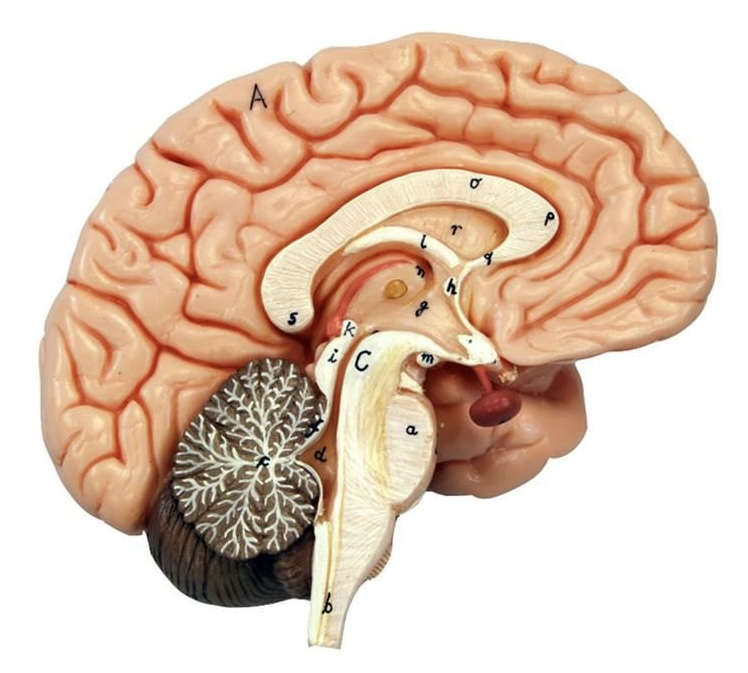

What is D?

lateral ventricle

Imagine thin membrane separating the 2 lateral ventricles

septum pellucidum

What is C?

3rd ventricle

What is B?

cerebral aqueduct

What is A?

4th ventricle

What is below A at the very end?

central canal (spinal cord)

What is C?

midbrain

tectum (corpora quadrigemina): superior colliculus

tectum (corpora quadrigemina): inferior colliculus

What is a?

pons

medulla oblongata

intermediate mass of thalamus

hypothalamus

What is the pink bulb?

pineal gland

corpus callosum

fornix

What is A?

cerebral cortex

cerebral tracts

cerebral hemispheres

longitudinal fissure

What are these ridges?

gyri

What are these shallow grooves?

sulci

Divides parietal from frontal lobe

central sulcus

precentral gyrus

postcentral gyrus